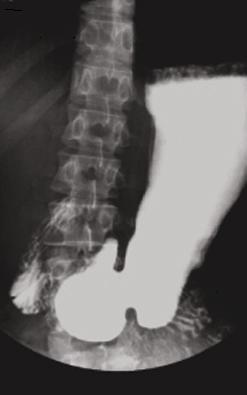

TOGD duodenum debout :

images en serie de D1, genus superieure , D2 , genus

inferieure , D3 et D4 . Angle de Treizt est en vue

arriere de angle de petit courbure . Bulbe est en

pleine de baryte et se voyait normalement |

Arcade duodenum et antrum :

Images TOGD avec compression de la region bulbaire . |

Estomac , antrum

, pylore et ---arcade

duodenum en profile . |